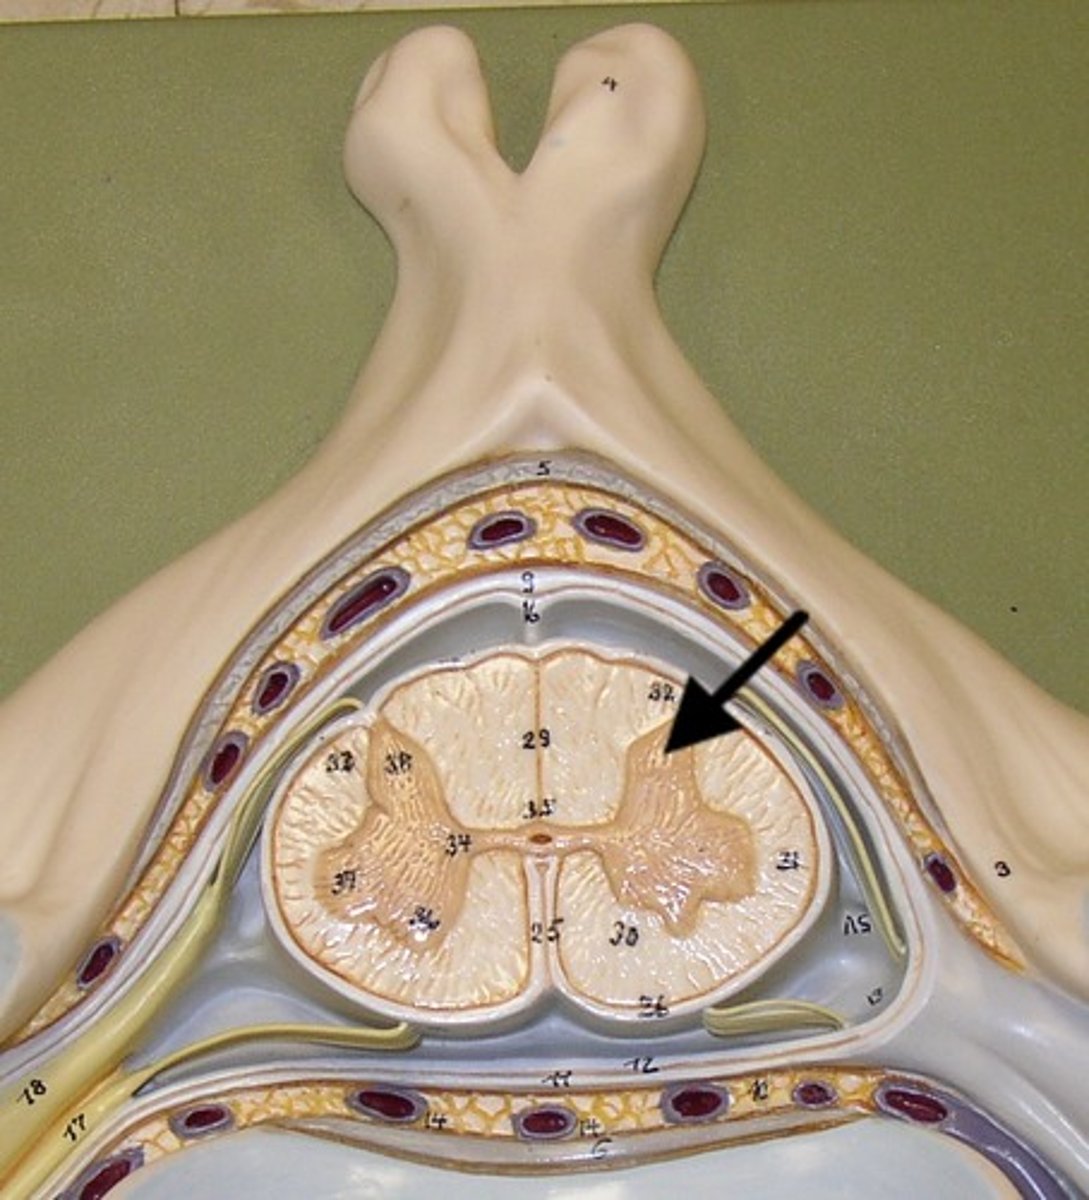

Anterior gray horn

lateral gray horn

posterior gray horn

anterior white column

posterior white column

lateral white column

gray commissure

central canal

anterior median fissure